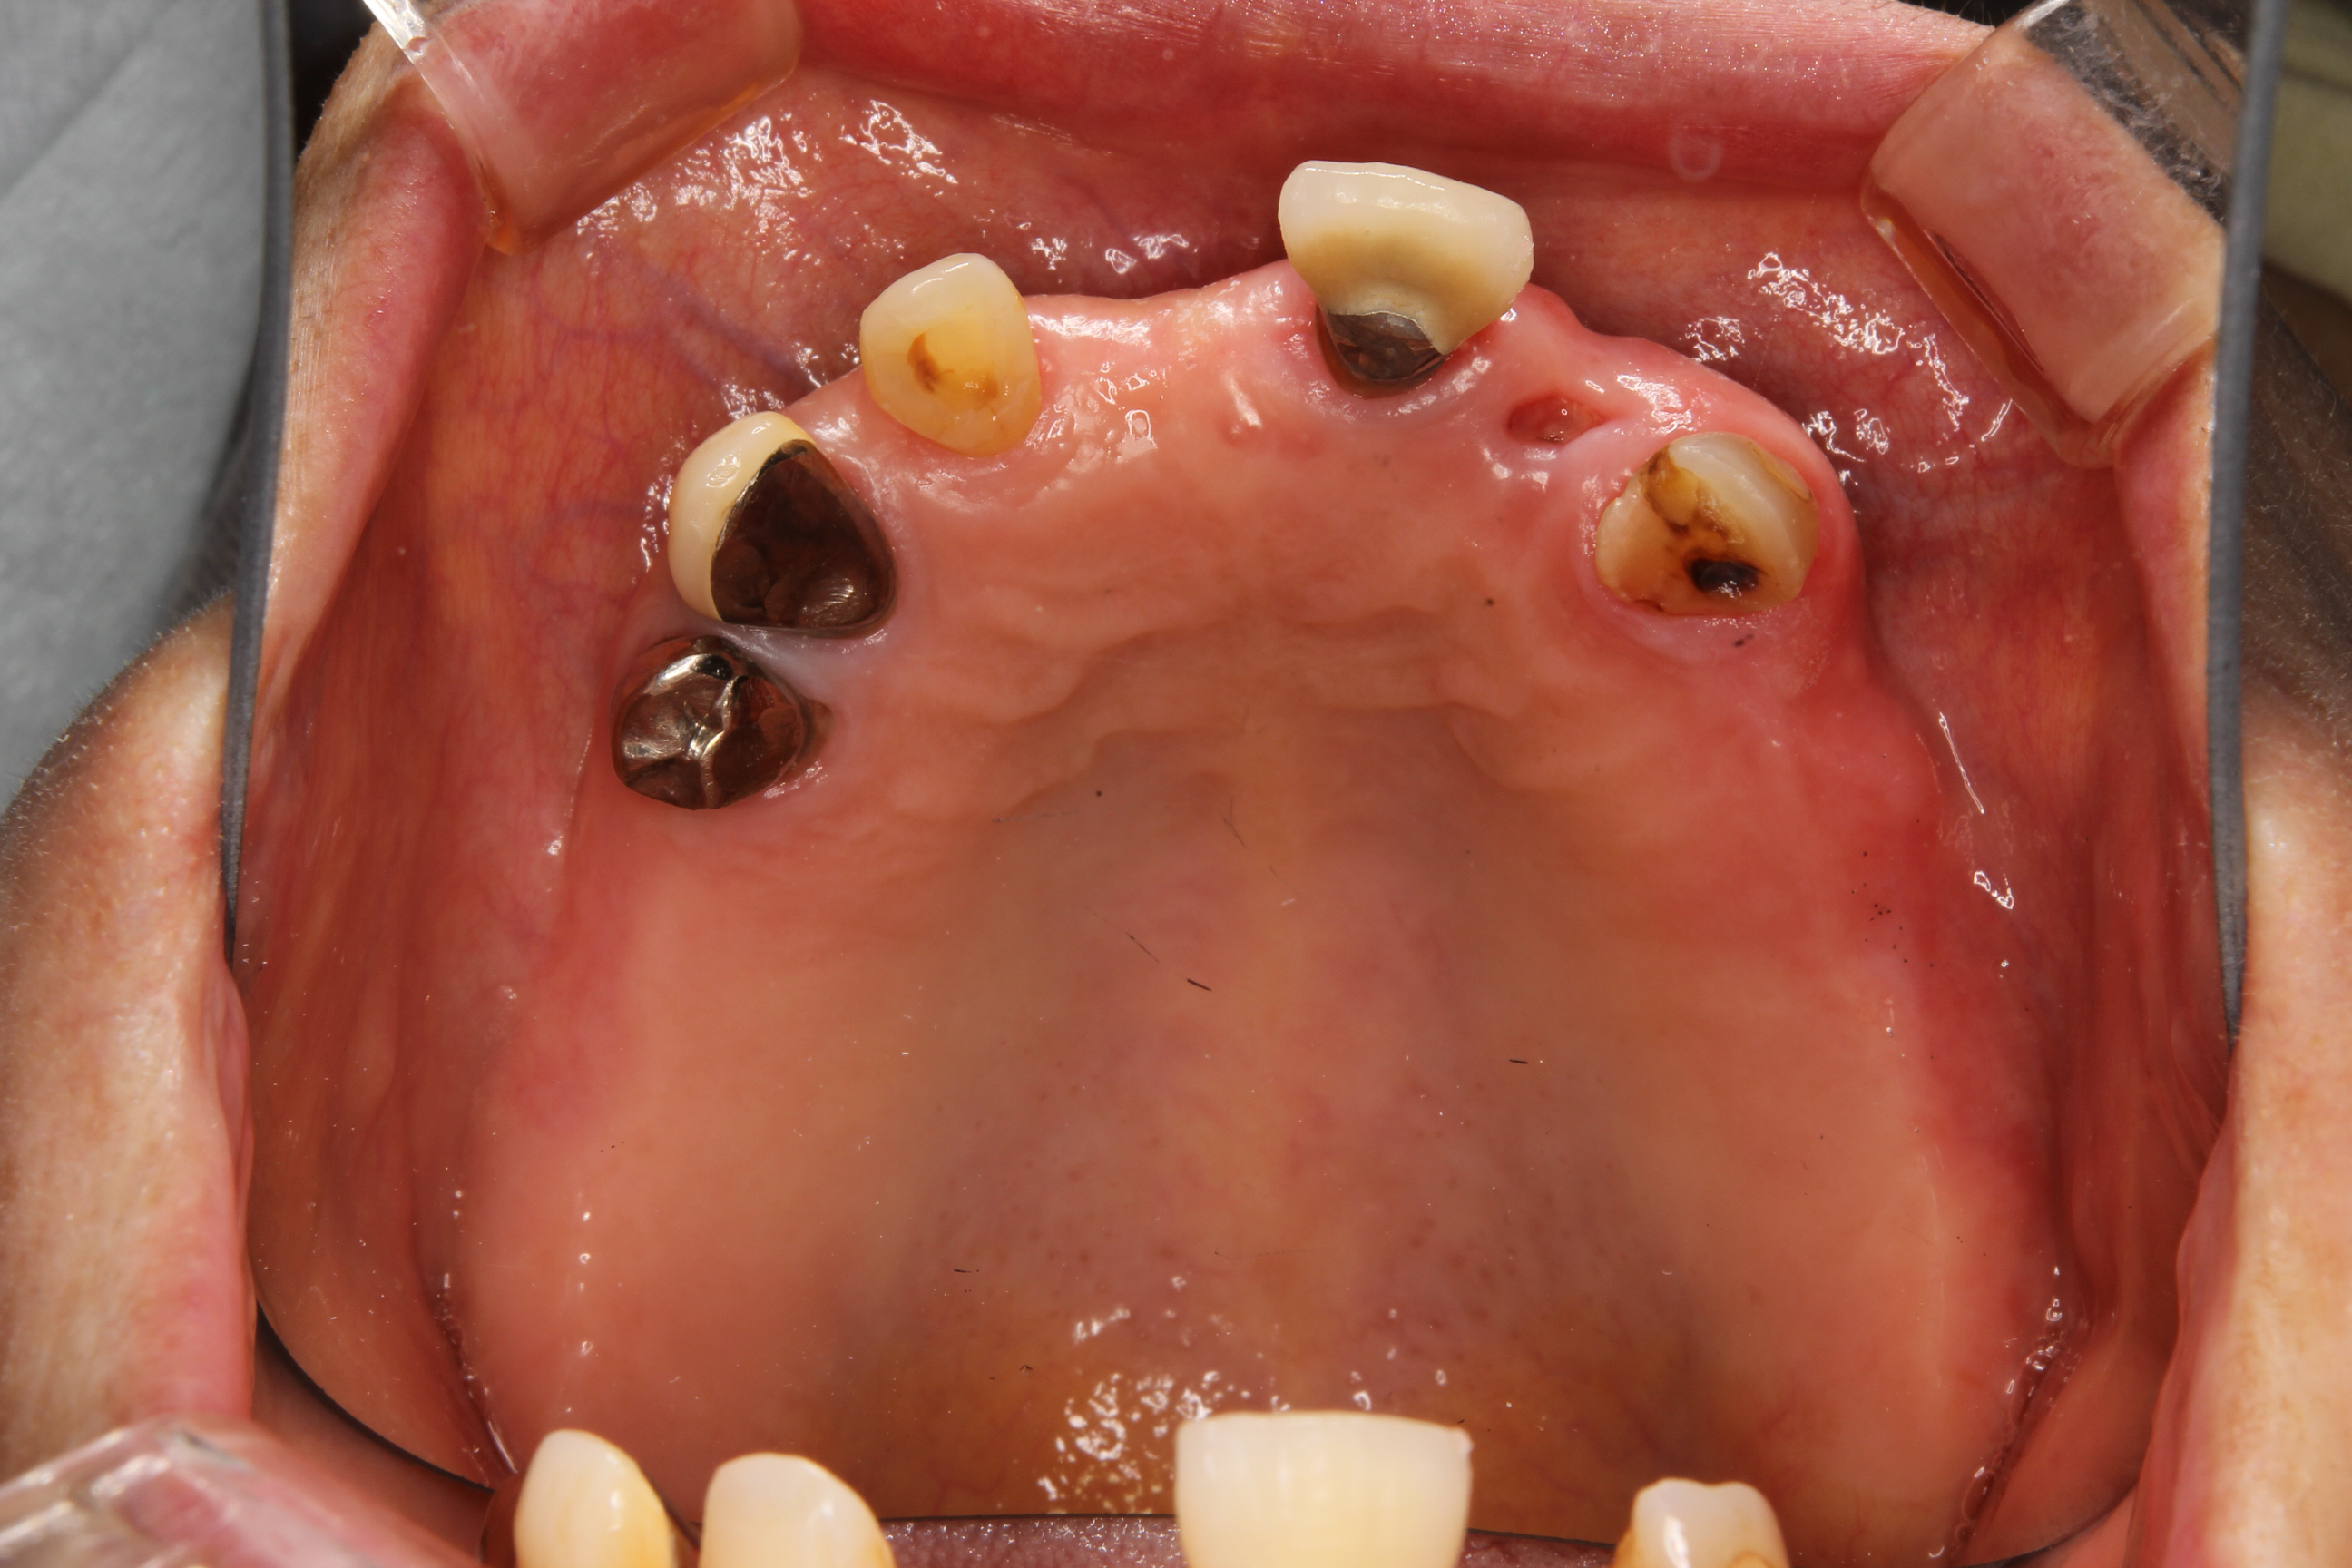

下の写真の患者さんも上下に部分義歯を装着しておりましたが、噛み合わせの不良により前歯部に負担がかかり、前歯が歯根破折により抜歯せざるをえない状態でした。

また、残存している天然歯も著しく摩耗していたり、病的に移動していたりします。

見た目においても、天然歯に被せてあるクラウンと義歯の調和はとれておらず、患者さんもとても気にされておりました。